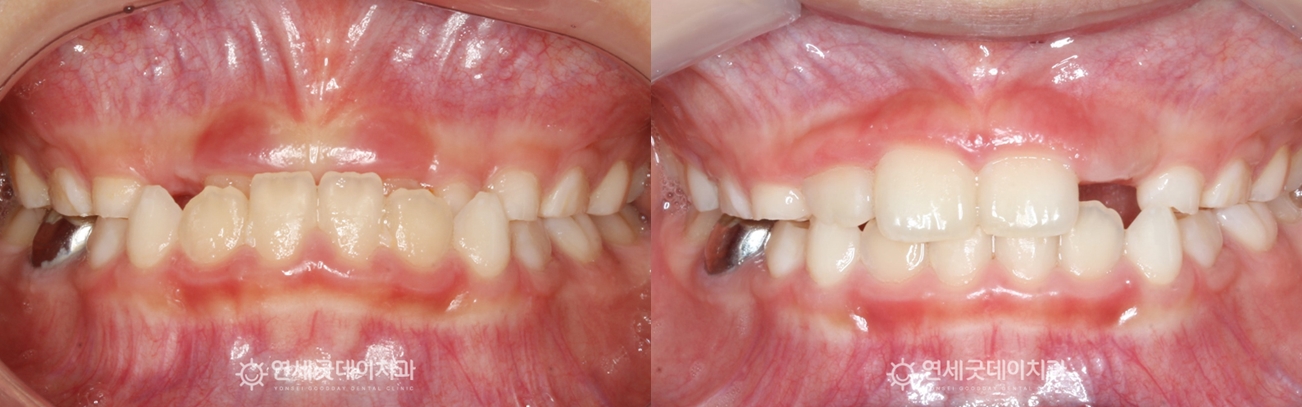

▲ 프리올소 치료후 (촬영시기 : 2025년 8월)

약 11개월 간의 프리올소 치료를 통해

더불어 얼굴의 균형을 잡아줌으로써 한층 자연스럽고 아이의 외모적인 자신감도 회복하였습니다.